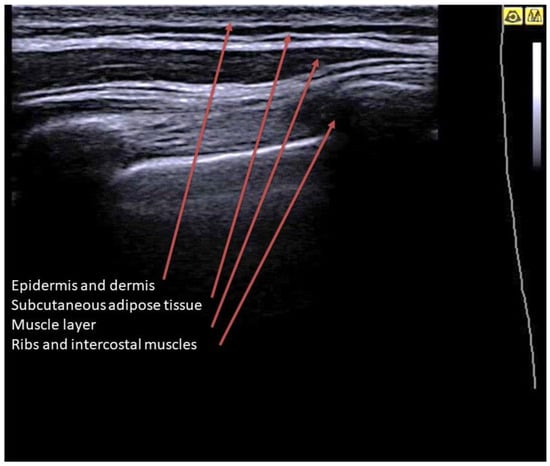

2. Basic Lung Ultrasound

3. Lung Ultrasound Evaluation

4. Lung Ultrasound on Physiological Lung